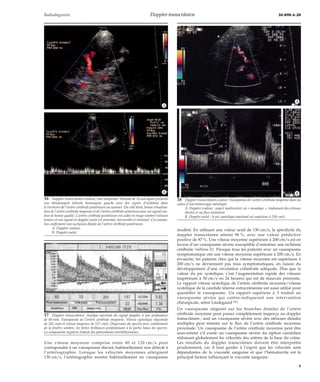

Une vitesse moyenne comprise entre 80 et 120 cm/s peut

correspondre à un vasospasme discret, habituellement non détecté à

l’artériographie. Lorsque les vélocités moyennes atteignent

130 cm/s, l’artériographie montre habituellement un vasospasme

*A

*B

modéré. En utilisant une valeur seuil de 130 cm/s, la spécificité du

doppler transcrânien atteint 96 %, avec une valeur prédictive

positive de 87 %. Une vitesse moyenne supérieure à 200 cm/s est en

faveur d’un vasospasme sévère susceptible d’entraîner une ischémie

cérébrale (tableau II). Presque tous les patients avec un vasospasme

symptomatique ont une vitesse moyenne supérieure à 200 cm/s. En

revanche, les patients chez qui la vitesse moyenne est supérieure à

200 cm/s ne deviennent pas tous symptomatiques, en raison du

développement d’une circulation collatérale adéquate. Plus que la

valeur du pic systolique, c’est l’augmentation rapide des vitesses

(supérieure à 50 cm/s en 24 heures) qui est de mauvais pronostic.

Le rapport vitesse systolique de l’artère cérébrale moyenne/vitesse

systolique de la carotide interne extracrânienne est aussi utilisé pour

quantifier le vasospasme. Un rapport supérieur à 3 traduit un

vasospasme sévère qui contre-indiquerait une intervention

chirurgicale, selon Lindegaard [60].